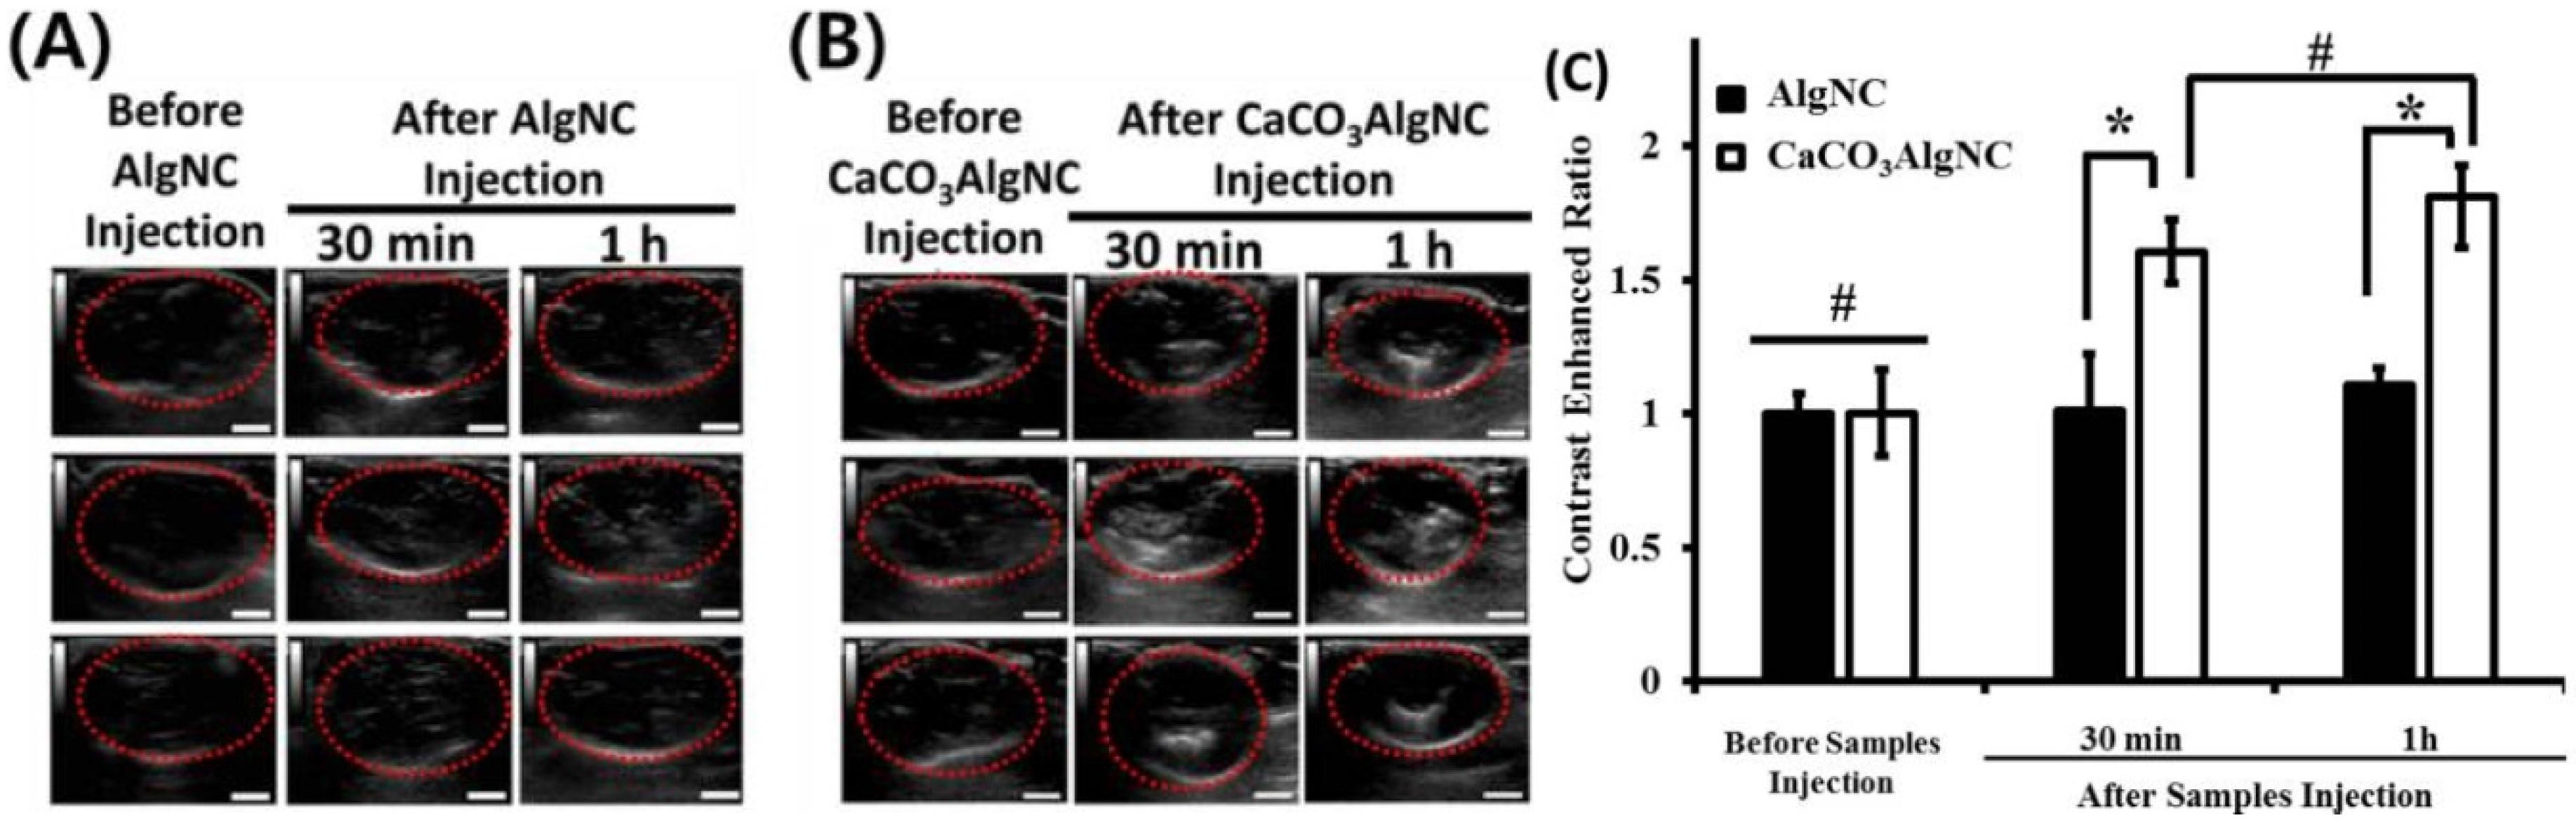

2.6. Drug/Gene Delivery